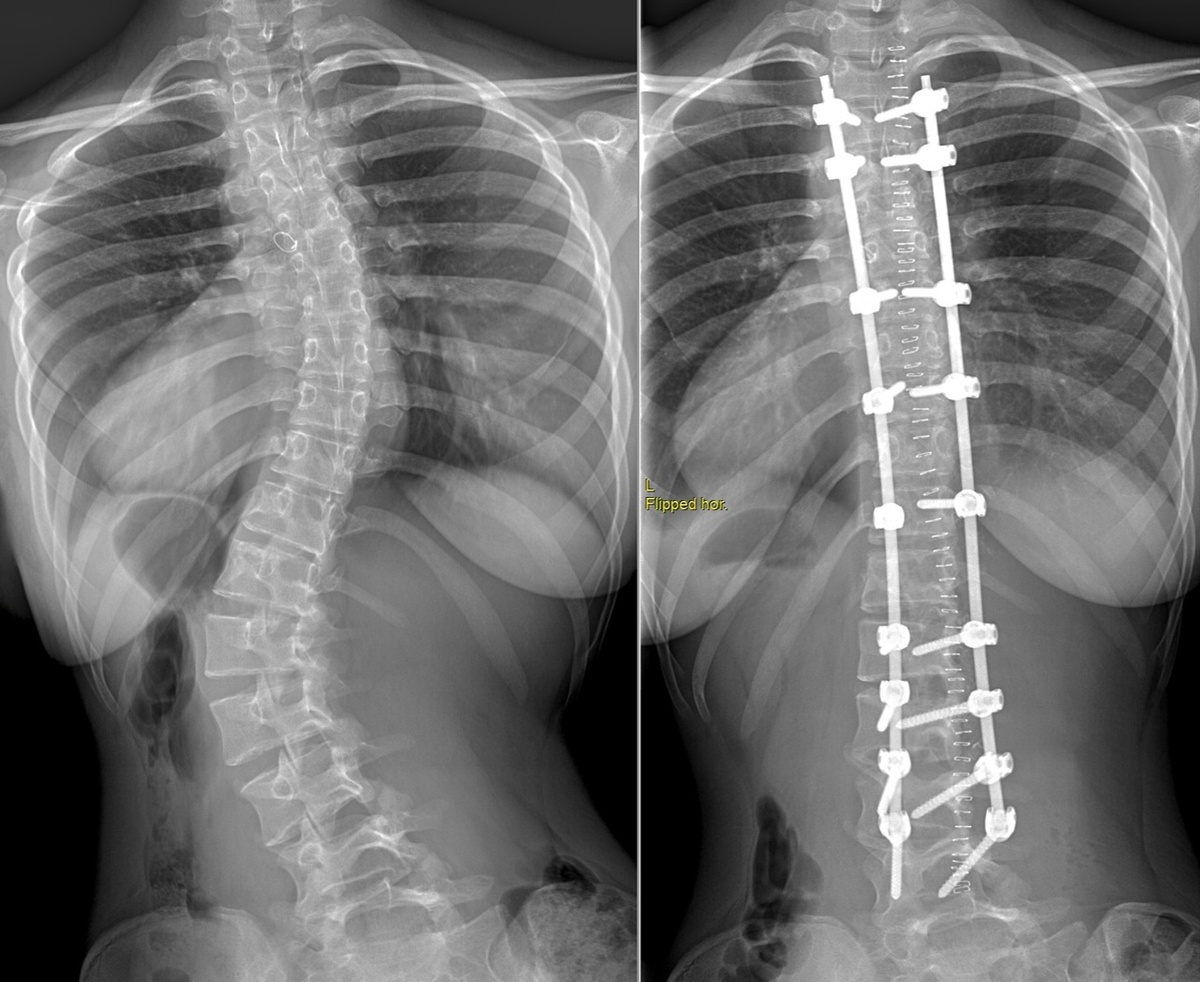

Сколиоз разделяют на четыре степени: первая (до 10 градусов искривления), вторая (до 25 градусов), третья (до 50 градусов) и четвёртая (свыше 50; в практике вертебрологов наблюдаются деформации и более 100 градусов). При сколиозе у пациентов может наблюдаться деформация рёбер или грудной клетки. При грубых деформациях от сдавления могут страдать внутренние органы пациента.

Хирургическое лечение сколиоза предполагает установку специальной металлоконструкции на всю жизнь

Сколиоз третьей и особенно четвёртой степени исправляется хирургическим путём. Операция проходит в один этап: хирурги имплантируют шурупы в позвонки, затем соединяют их стержнями. Специальная металлоконструкция позволяет достичь оптимальной коррекции позвоночника прямо во время операции.

Благодаря коррекции пациенты «вырастают» на несколько сантиметров, спина выравнивается, и талия становится тоньше — особенно этот эстетический эффект важен для девочек-подростков.

Металлоконструкция устанавливается на всю жизнь.